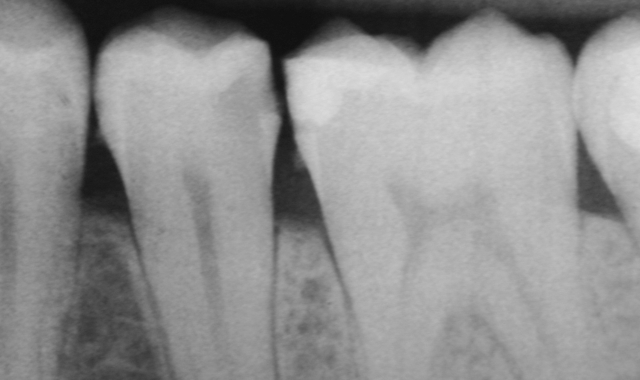

How to use liner for pulpal protection in restorative dentistry

Liners are frequently used beneath dental restorations to reduce the potential for post-operative sensitivity but take on a much greater role long-term in serving as pulpal protectants.

Clinical case: The patient presents with a mandibular premolar with a large distal carious lesion. The caries were carefully excavated resulting in a deep preparation, especially on the axial wall …

Click here to read the full clinical case.